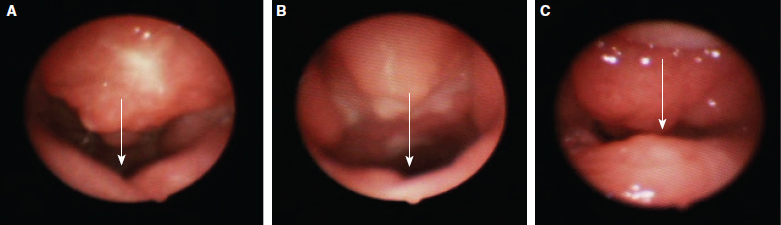

58 ○ Patients with velopharyngeal insufficiency and sagittal orientation of the levator veli palatini musculature are candidates for double-opposing Z-plasty. ○ Sagittal orientation of the levator veli palatini musculature is seen in patients with submucous cleft palate and in some patients with previously repaired cleft palate. ○ The orientation of the levator veli palatini can be ascertained on intraoral examination and confirmed on nasendoscopy during speech production. ○ Double-opposing Z-plasty is most likely to resolve velopharyngeal insufficiency in patients with small velopharyngeal gaps on preoperative nasendoscopy. ○ Double-opposing Z-plasty is unlikely to cause obstructive sleep symptoms. Establishing velopharyngeal function is the primary purpose of repairing clefts of the palate. Regardless of the surgical technique, velopharyngeal dysfunction (VPD) may occur after cleft palate repair. Surgical options to treat VPD include palatoplasty, sphincter pharyngoplasty, pharyngeal wall augmentation, and pharyngeal flap.1–4 The surgical recommendations for any particular patient are based on the degree of VPD, the status of the palate and velopharyngeal port, and surgeon preference. The goal of these interventions is to optimize velopharyngeal closure during speech without compromising the upper airway. Although surgical management of VPD is largely related to surgeon preference, the concept of tailoring the procedure to a patient’s needs is appealing. For patients with sagittal orientation of the levator veli palatini (LVP) muscles, such as those with submucous cleft palate or previously repaired cleft palate, surgical procedures to reposition the LVP into a transverse orientation may improve palatal function. Fig. 58-1 A, Preoperative abnormal insertion of the levator. B, Postoperative reorientation of the levator in a transverse direction. Leonard Furlow5 described a technique for repair of cleft palate that incorporates a Z-plasty on the nasal surface of the velum and an opposing Z-plasty on the oral surface of the muscular palate. Originally described for repair of cleft palate, the double-opposing Z-plasty has also been used to correct VPD.5–7 It offers specific advantages by repositioning the LVP muscles transversely with velar Z-plasties, resulting in reorientation of the LVP musculature and palatal lengthening (Fig. 58-1). D’Antonio et al8 showed that realignment of the levator musculature with double-opposing Z-plasty improved palate motion, lengthened the palate, and thickened the middle of the soft palate. Furthermore, the likelihood of postoperative obstructive sleep apnea is very low after double-opposing Z-plasty, which makes it particularly well suited for patients with VPD and sagittal orientation of the LVP.9 Velopharyngeal closure is necessary for normal speech production. VPD is characterized by hypernasal resonance and nasal air emission, which can compromise speech intelligibility. VPD is often associated with cleft palate, previously repaired cleft palate, or submucous cleft palate. Less commonly, it may be acquired after adenoidectomy or result from progressive neuromuscular disease. In patients with unrepaired clefts of the palate, the LVP fibers lay in the sagittal position, with abnormal insertion onto the posterior margin of the hard palate.10,11 In patients with previously repaired clefts of the palate, who may have had a straight-line palate repair or incomplete intravelar veloplasty (IVVP), persistent sagittal orientation of the LVP may compromise palate elevation. Intuitively, restoring the physiologic orientation of the LVP to treat VPD in patients with a sagittally oriented LVP is desirable.12,13 Chen et al7 and others have shown favorable outcomes (97% to 100%) when using the double-opposing Z-plasty in patients with sagittal LVP and small velopharyngeal gaps on fluoroscopy. When reviewing a large series of patients with a sagittally oriented LVP, VPD, and a range of preoperative gap sizes, Perkins et al9 demonstrated that the likelihood of resolution of VPD after double-opposing Z-plasty was related to gap size. Specifically, patients with a gap larger than 50% were less likely to have resolution of VPD after double-opposing Z-plasty than patients with smaller gaps. Diagnosis of VPD should include perceptual evaluation by a speech-language pathologist, who generates a speech differential diagnosis. Patients with velopharyngeal mislearning or other speech disorders, such as childhood apraxia, should receive speech therapy. Patients with velopharyngeal insufficiency or inadequacy (VPI) should have an instrumental assessment with nasendoscopy (Fig. 58-2). The endoscopic finding of a notch on the dorsal aspect of the velum during speech production confirms the sagittal orientation of the LVP9 (see Fig. 58-2, A). In some patients with previously repaired cleft palate, extensive scarring of the muscular palate may obscure the characteristic notch (see Fig. 58-2, B). In contrast, the endoscopic appearance of an anatomically normal muscular palate is characterized by a central bulging of the palate (see Fig. 58-2, C). On intraoral examination during phonation or gagging, the sagittal orientation of the LVP results in a vaulted V-shaped pattern of velar elevation, in contrast to the normal transverse elevation of the velum. This physical finding is very similar to that seen in patients with submucous clefts of the palate, because the physiology and orientation of the LVP is similar. This vaulted V-shaped pattern of velar elevation is the intraoral finding that corresponds to the notching on the dorsal aspect of the velum seen on nasendoscopy. The orientation of the LVP, the gap size as a percent of velopharyngeal area at rest, presence of Passavants ridge, and aberrant pulsations are evaluated on endoscopy.14 The Golding-Kushner scale is applied to the endoscopic examination to describe the degree of lateral wall and palatal movement during speech production relative to rest.15 Velopharyngeal gap larger than 50% is defined as large, 20% to 50% is considered moderate, and smaller than 20% is classified as small. The basal view of multiview videofluoroscopy may be helpful in demonstrating the dorsal notch. However, the basal view is the most difficult view to obtain. For this reason, we reserve multiview fluoroscopy for patients with VPD and transverse orientation of the LVP. In our protocol, patients with sagittal LVP muscles, VPI, and small or medium gaps (smaller than 50%) are treated with a double-opposing Z-plasty.